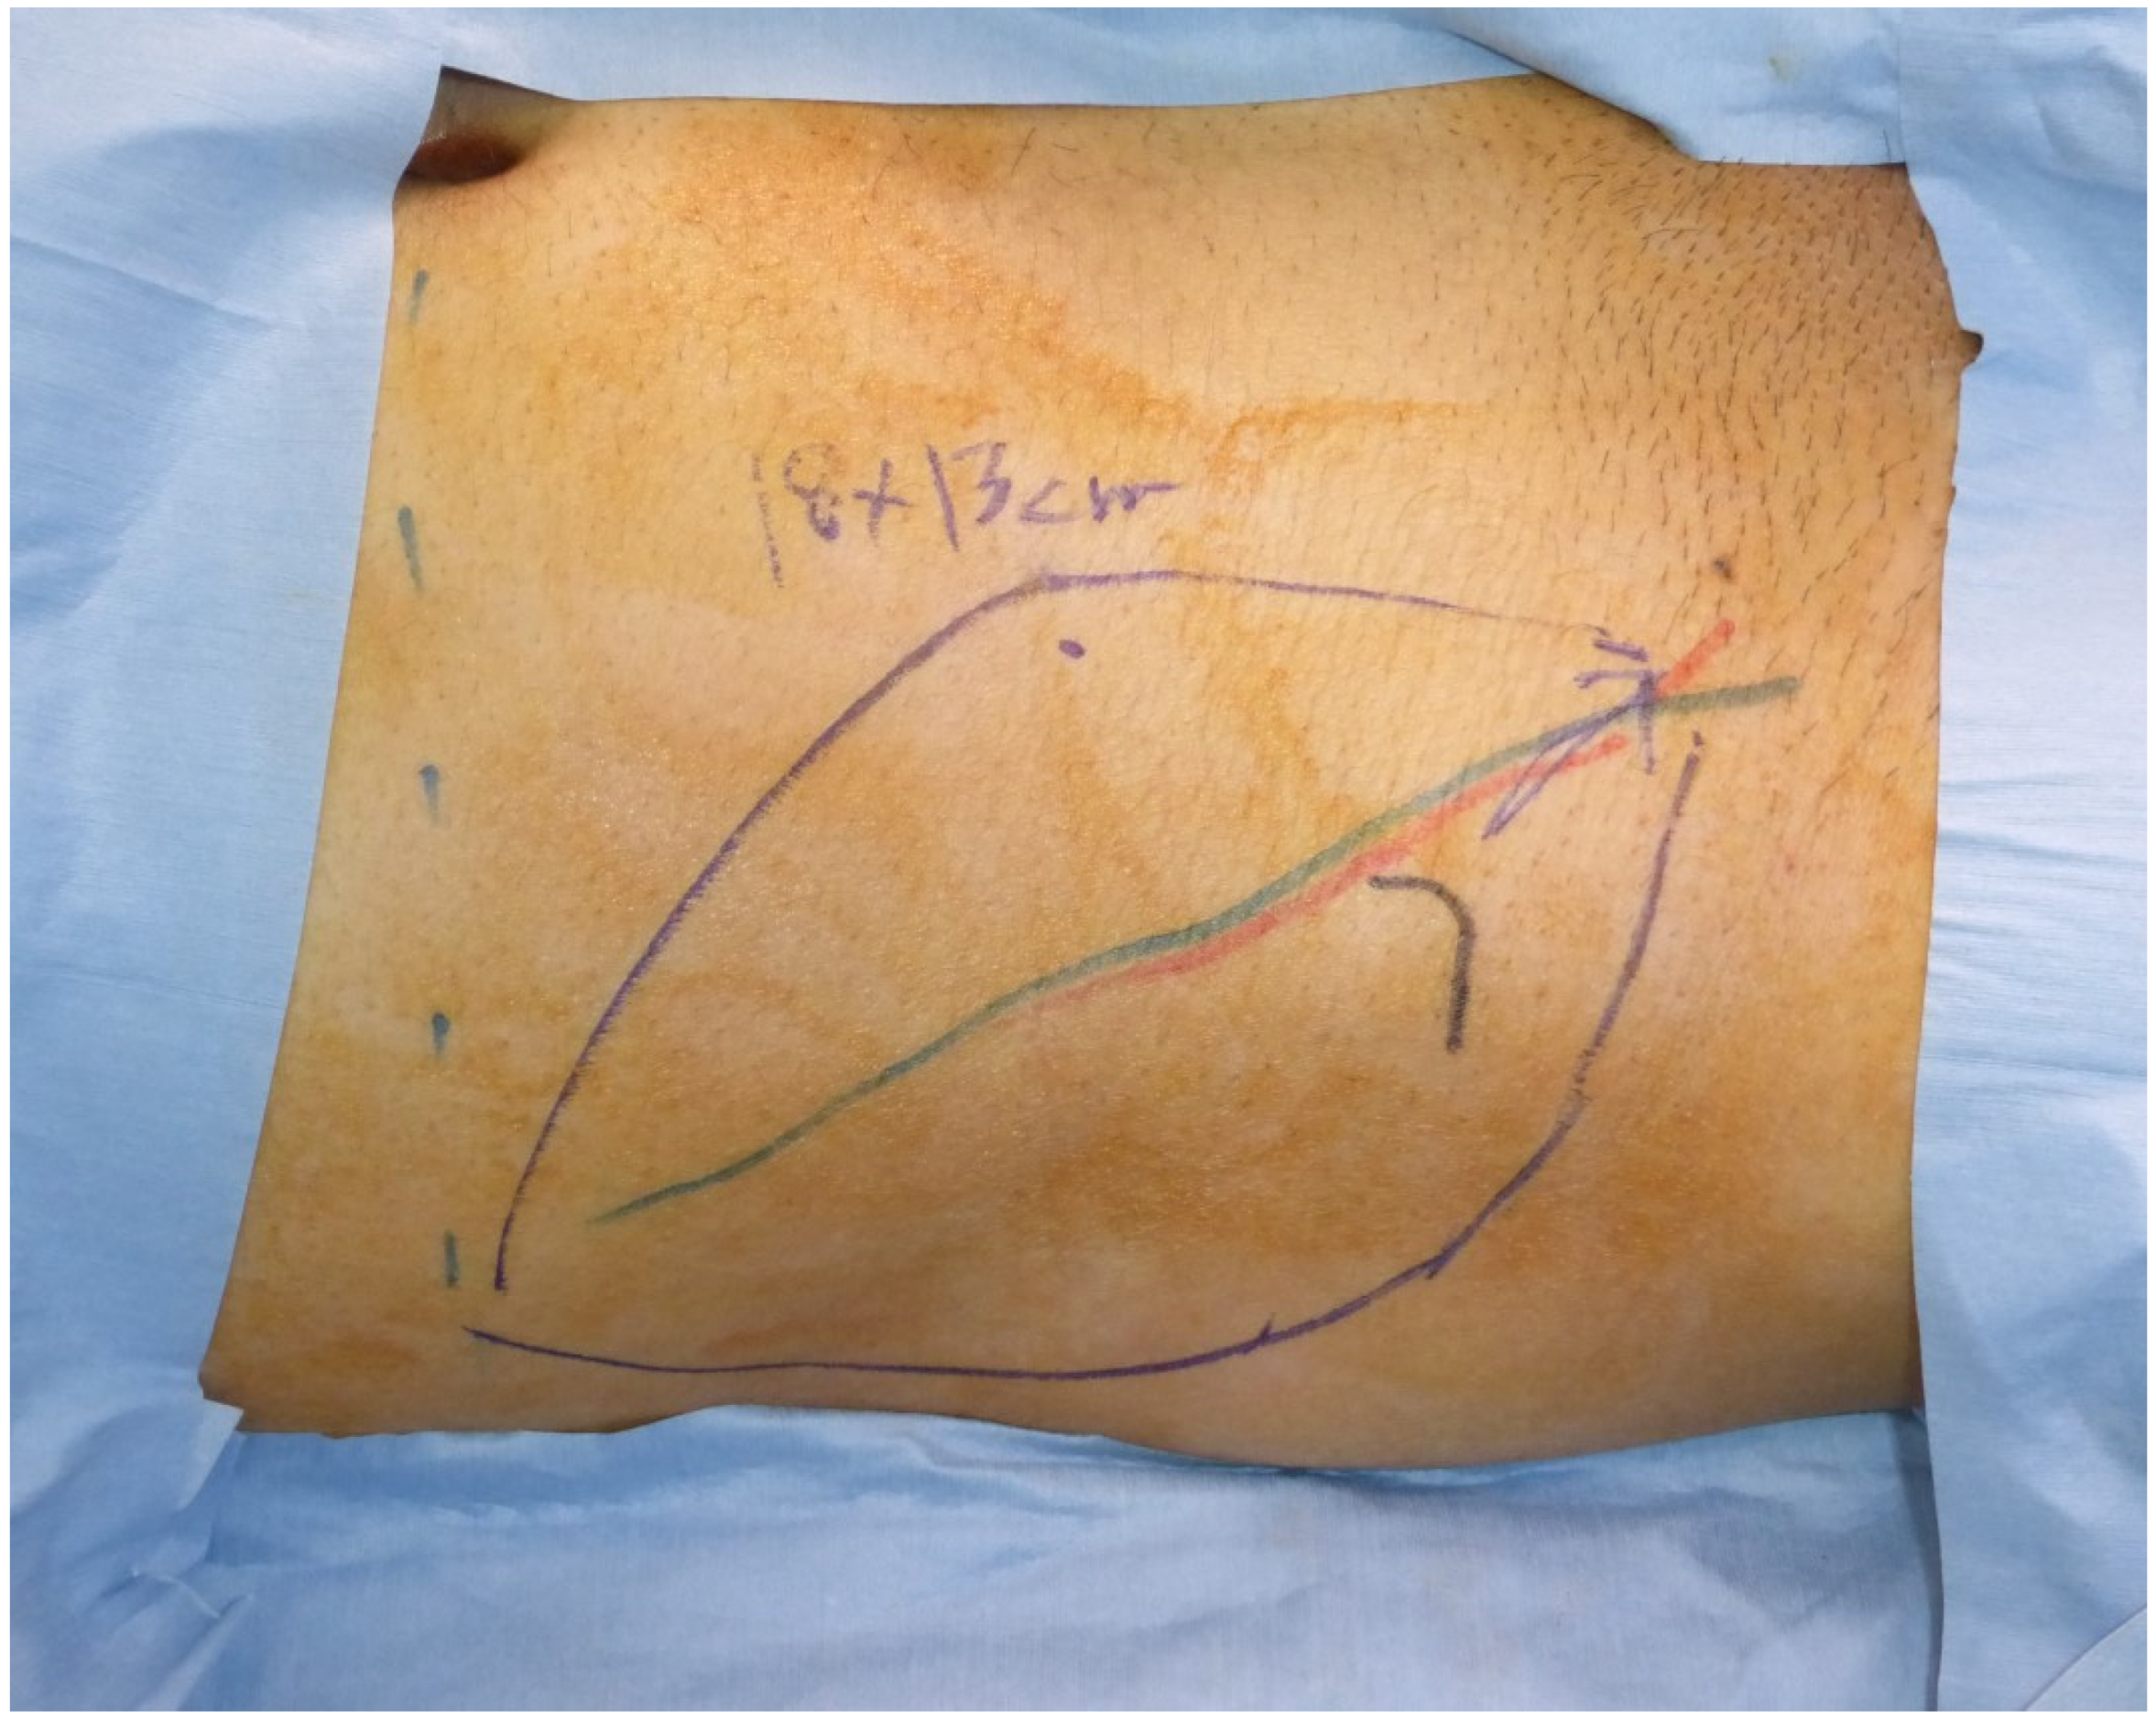

A forty-one-year-old man had wide excision of a soft tissue tumor in the left groin. An SCIP flap of 18 × 13 cm based on the superficial branch of the SCIA was harvested in the contralateral groin region (Figure 2). The skin flap was elevated saving the deep soft tissue (Figure 3) and transferred to the defect. The flap survived completely (Figure 4). A suction drain was removed on postoperative day seven. No donor-site morbidity developed (Figure 5).

Figure 2.

An 18 × 13 cm SCIP flap was designed based on a preoperative marking of the superficial branch of the SCIA.